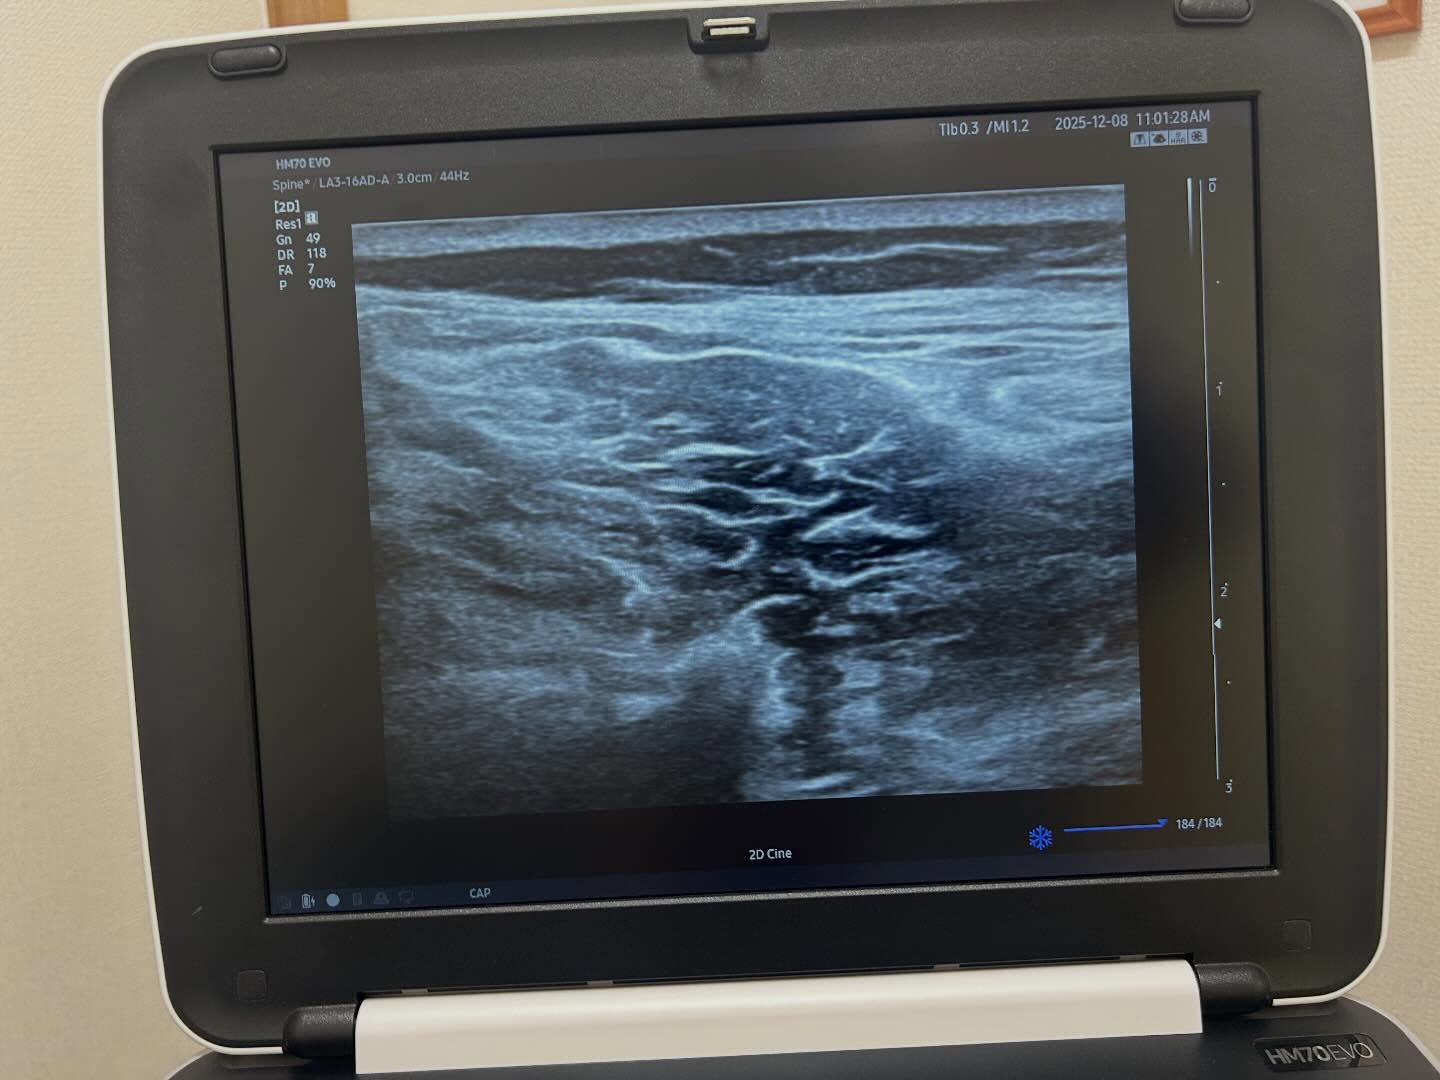

坂道で転倒して腰を強打した50代女性の患者さん。

近医にてレントゲン上骨折が無いと言われたとの事で来院されました。話を聞いて、触った瞬間、99%の自信がありました。

そしてエコーを撮って99.9%の自信になりました。患者さんに前述の特徴をお伝えして、所見との一致点が多いことも説明した上で精密検査をしたところ、、、やはり骨折してました!